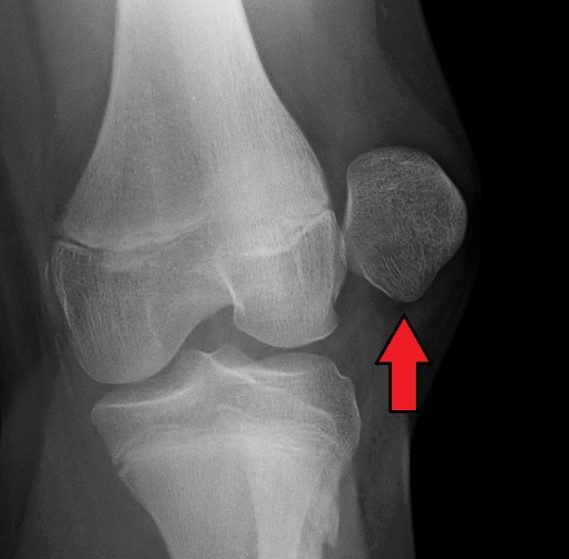

가장 심각한 슬개골 탈구의 증상 중 하나는 무릎의 가시적인 변형일 수 있습니다. 슬개골이 원래 위치에서 크게 이동한 경우, 무릎의 형태나 구조가 훼손되어 보일 수 있습니다. 이는 무릎 뒷부분이 비정상적으로 부풀어 오르거나, 무릎이 정상적인 위치보다 앞으로 또는 뒤로 늘어나 보이는 형태로 나타날 수 있습니다.

■ 슬개골 재배치

이 방법은 슬개골이 너무 멀리 이동하여 제 자리에 돌아가지 않는 경우에 사용됩니다. 수술 중에 의사는 슬개골을 원래 위치로 밀어 넣으며, 필요한 경우 인대나 힘줄을 재건할 수도 있습니다.